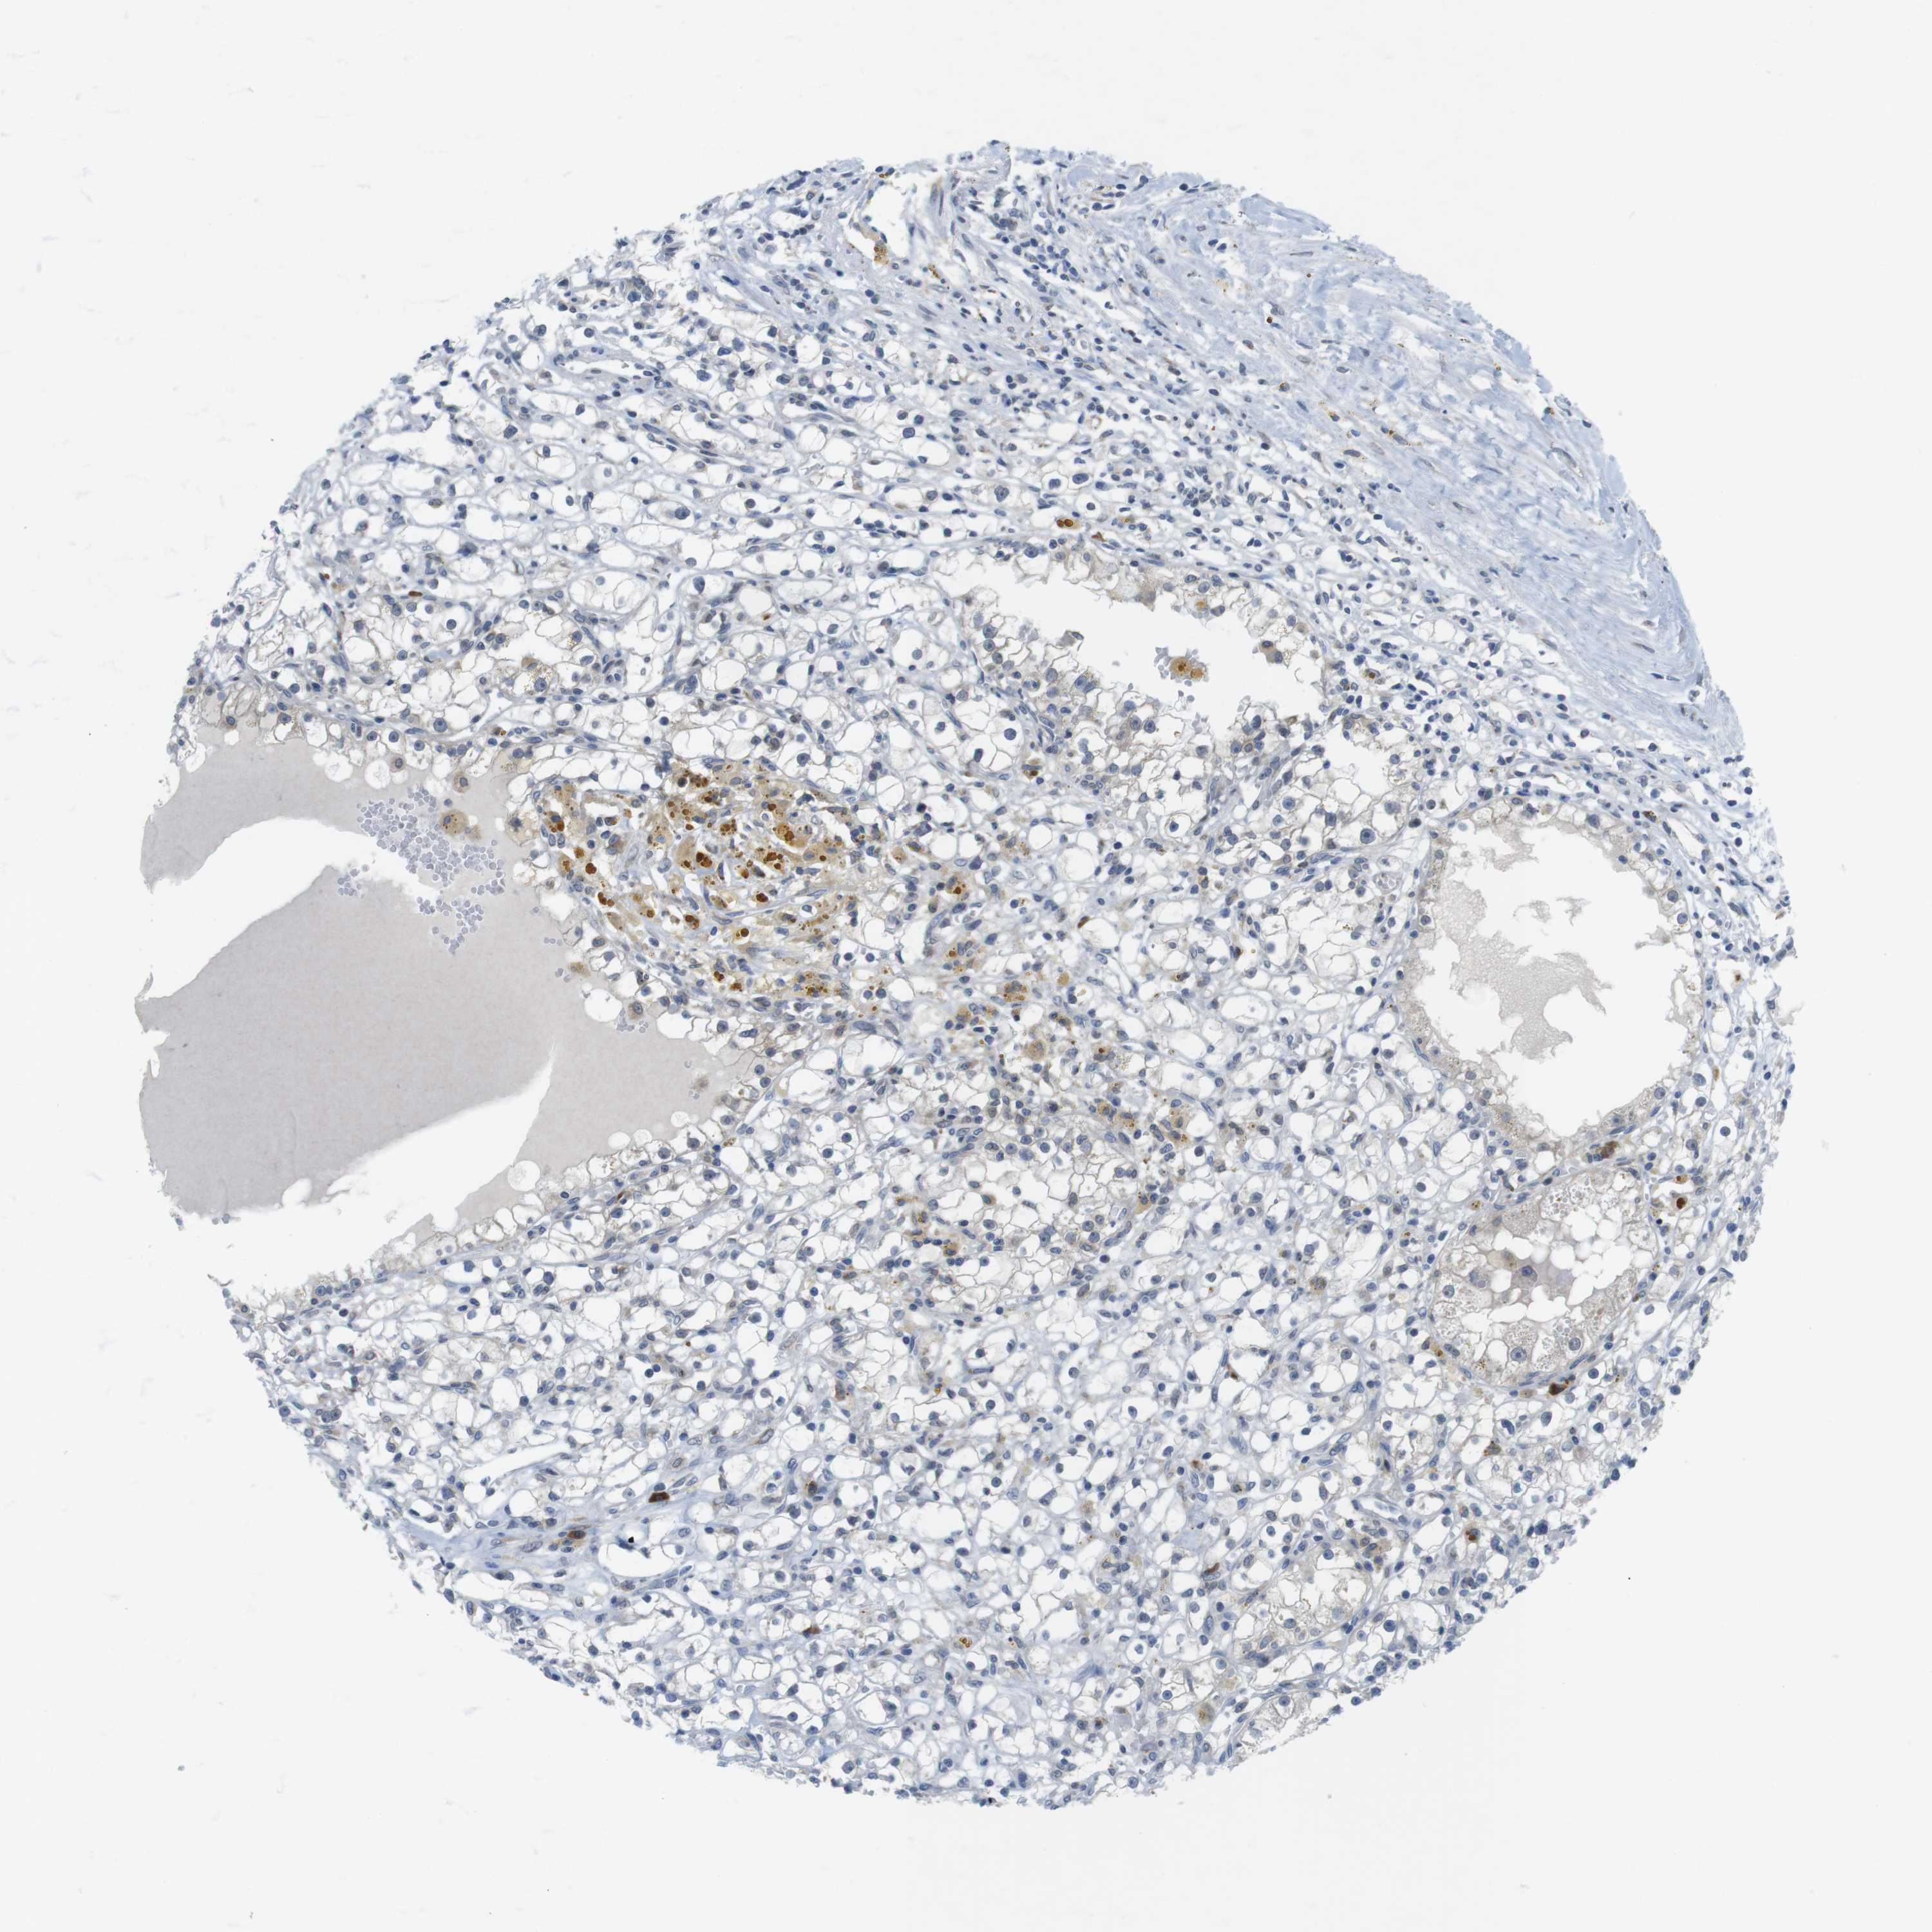

KIDNEY RENAL PAPILLARY CELL CARCINOMA (TCGA) - Interactive survival scatter ploti

The Survival Scatter plot shows the clinical status (i.e. dead or alive) for all individuals in the patient cohort, based on the same data that underlies the corresponding Kaplan-Meier plots. Patients that are alive at last time for follow-up are shown in blue and patients who have died during the study are shown in red.

The x-axis shows the expression levels (FPKM) of the investigated gene in the tumor tissue at the time of diagnosis. The y-axis shows the follow-up time after diagnosis (years). Both axes are complimented with kernel density curves demonstrating the data density over the axes. The top density plot shows the expression levels (FPKM) distribution among dead (red) and alive patients (blue). The right density plot shows the data density of the survived years of dead patients with high and low expression levels respectively, stratified using the cutoff indicated by the vertical dashed line through the Survival Scatter plot. This cutoff is automatically defined based on the FPKM cutoff that minimizes the p-score. The cutoff can be changed by dragging the vertical line or by entering a cutoff value in the square labeled "Current cut-off".

Under the Survival Scatter plot the p-score landscape (black curve; left axis) is shown together with dead median separation (red curve; right axis). Dead median separation is the difference in median mRNA expression between patients who have died with high and low expression, respectively. It is calculated as follows: median FPKM expression of dead patients with high expression - median FPKM expression of dead patients with low expression. This is intended to aid the user in visually exploring custom cutoffs and the associated p-scores and dead median separation.

Individual patient data is displayed and can be filtered by clicking on one or more of the category buttons on the top of the page. Categories describing expression level and patient information include: high, low, alive, dead, female, male and tumor stages. The scale of the x-axis can be toggled between linear and log-scale by clicking on the "x log" button. Mouse-over function shows TCGA ID, patient information and mRNA expression (FPKM) for each patient.

& Survival analysisi